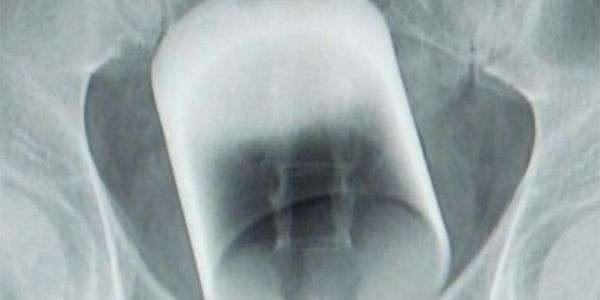

Ärzte in Guangzhou (China) staunten nicht schlecht, als sie das Röntgenbild eines Patienten zu Gesicht bekamen. Denn im Enddarm des Mannes steckte